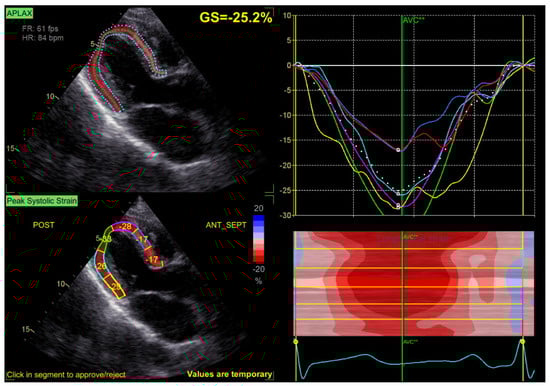

3.2. GLS at Baseline and during Follow-Up

| LVS GLS, % | 22. 3 ± 2.1 | 19.5 ± 3.1 | 19.1 ± 3.7 | 0.024/0.019 |